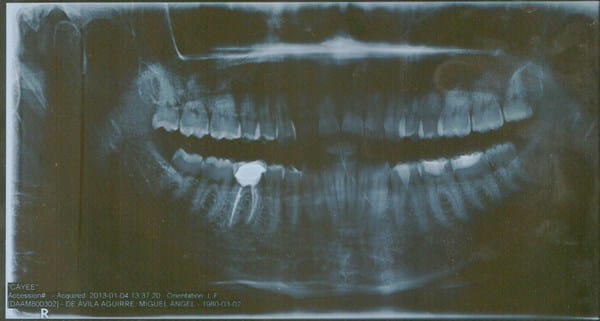

Fui con la endodoncista que me atendió y me dio antibióticos y antiinflamatorios y me pidió que me sacara una radiografía panorámica donde salen todos los dientes porque en la radiografía común no aparecía la infección pero la sorpresa fue cuando en la radiografía panorámica tampoco apareció nada! La radiografía la tomaron en plena inflamación!

Sin embargo, siento una pequeña "bolita" por debajo de la encía, mas bien sería en la mandíbula. La muela afectada es del lado derecho inferior, es la tercera de atrás hacia adelante.

P.D. Adjunto escaneos de la radiografía.